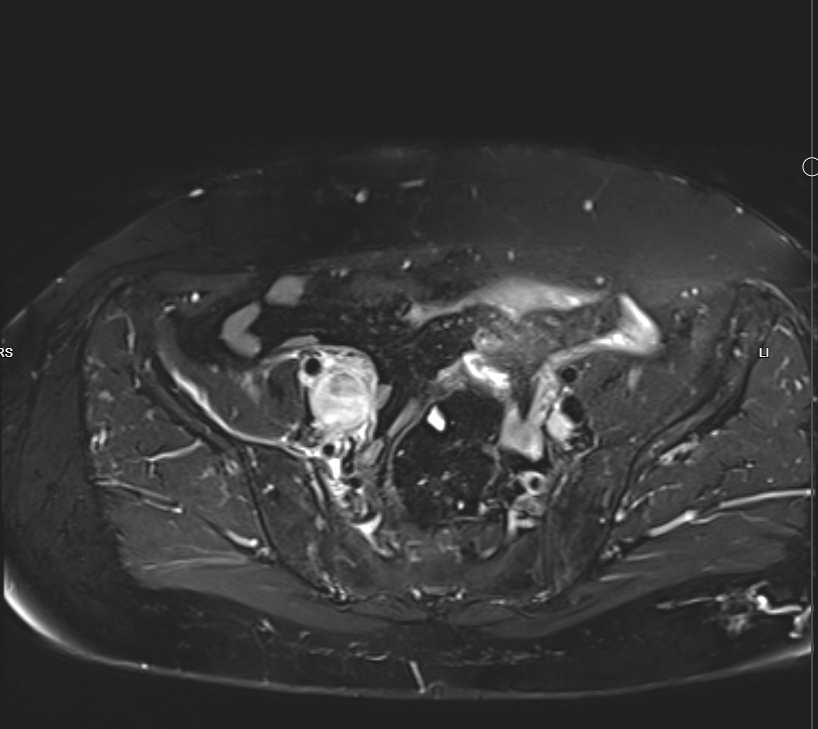

Pelvic MRI With IV Gd:

- Evidence of 7.5 X 4cm mass involves Rt side of uterus reaches endometrium, involves whole thickness of uterus and extends to Rt adnexa, also infiltration of peritoneal reflesion in Rt side of rectouterine pouch, shows marked DWI restriction, picture is suggestive of malignant tumor ?lymphoma ?sarcoma

- Single Lt internal iliac pathological LN, 18mm in short axis diameter, its signal is like uterine mass.

- There is also 26 X 22mm lesion in Rt internal iliac region, but heterogeneous signal ?pathological LN with necrosis